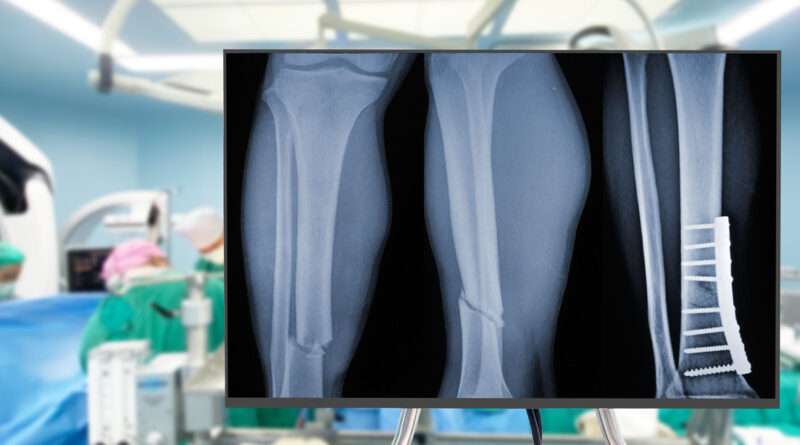

- Su tecnología es capaz de unir y fijar con precisión fragmentos óseos en minutos y con una incisión mínimamente invasiva. Gracias a su tecnología adhesiva, el pegamento, bautizado como Bone 02, ha logrado unir y fijar en unos pocos minutos distintos fragmentos óseos mediante una incisión de 2 a 3 centímetros que resulta mínimamente invasiva.

Gracias a su tecnología adhesiva, el pegamento, bautizado como Bone 02, ha logrado unir y fijar en unos pocos minutos distintos fragmentos óseos mediante una incisión de 2 a 3 centímetros que resulta mínimamente invasiva.

El material, inspirado en las ostras, representa un avance significativo respecto de los procedimientos tradicionales, que utilizan placas de metal para recuperar los huesos atendidos.